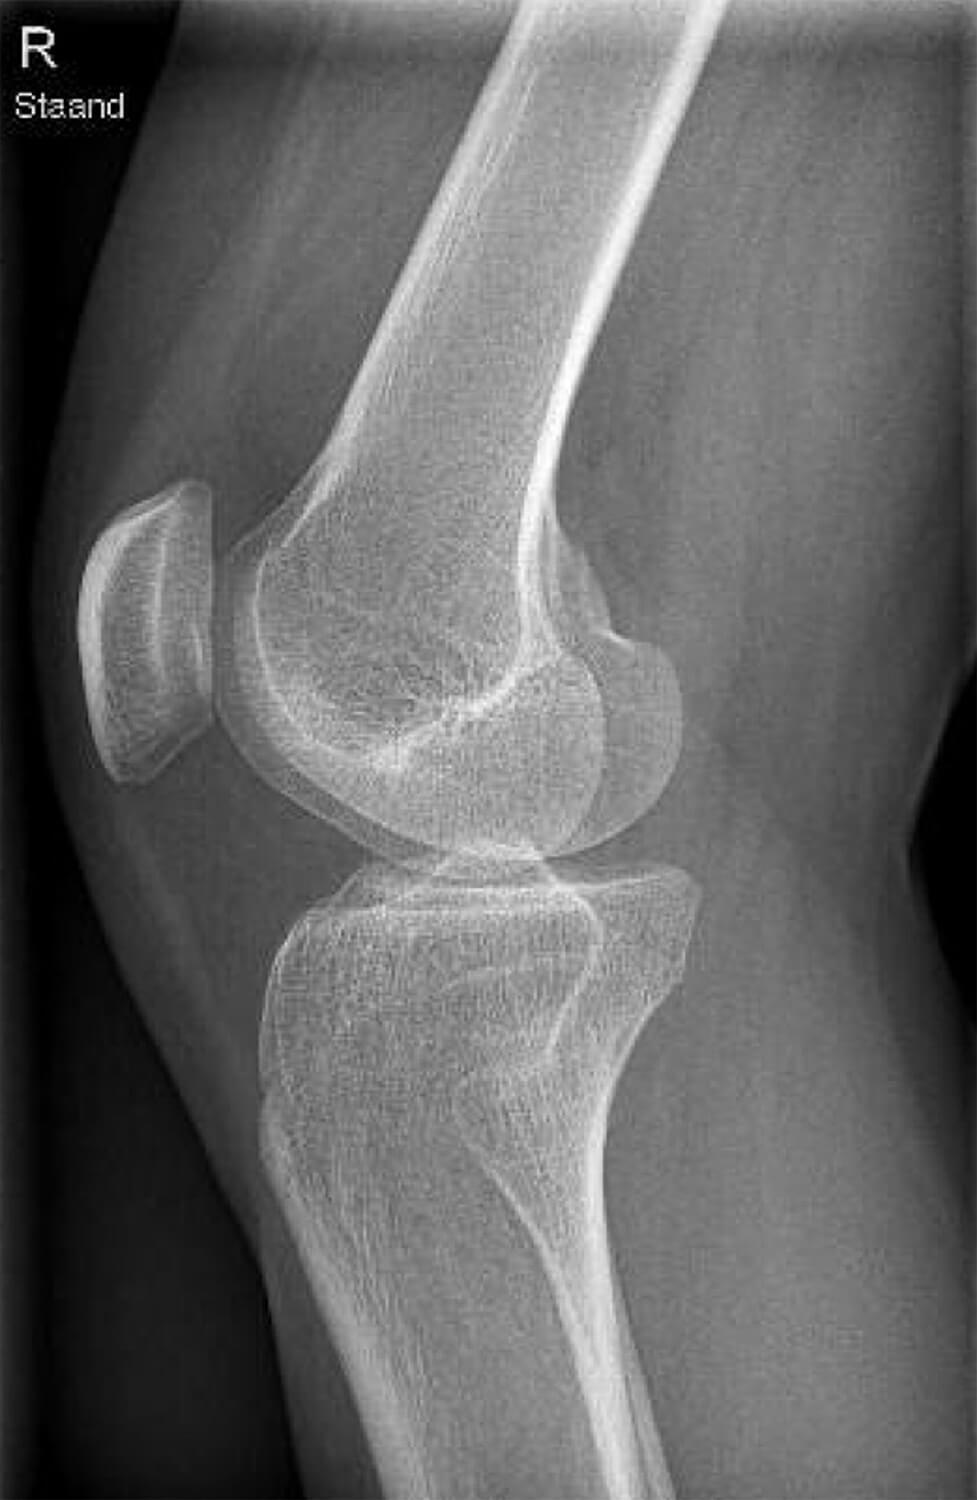

Met een röntgenfoto wordt gekeken naar de positie van de knieschijf ten opzichte van het bovenbeen. Door middel van dit onderzoek kan onder andere bekeken worden of de knieschijf niet te hoog staat (patella alta) of dat de knieschijf niet te veel naar buiten staat.

Deze röntgenfoto van de zijkant van de knie laat een normale positie van de knieschijf zien.